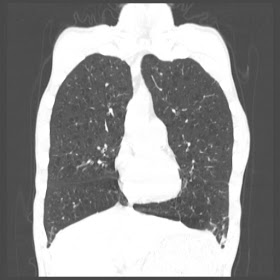

A 52 Years old man suffering with chest pain since 3 years

HRCT Chest